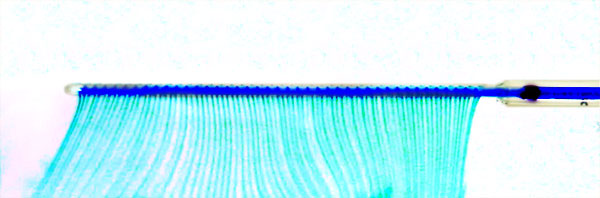

Figure 1 — OmniArray™ PBIC delivery

of dye solution in a water bath with a 5 cm porous length.